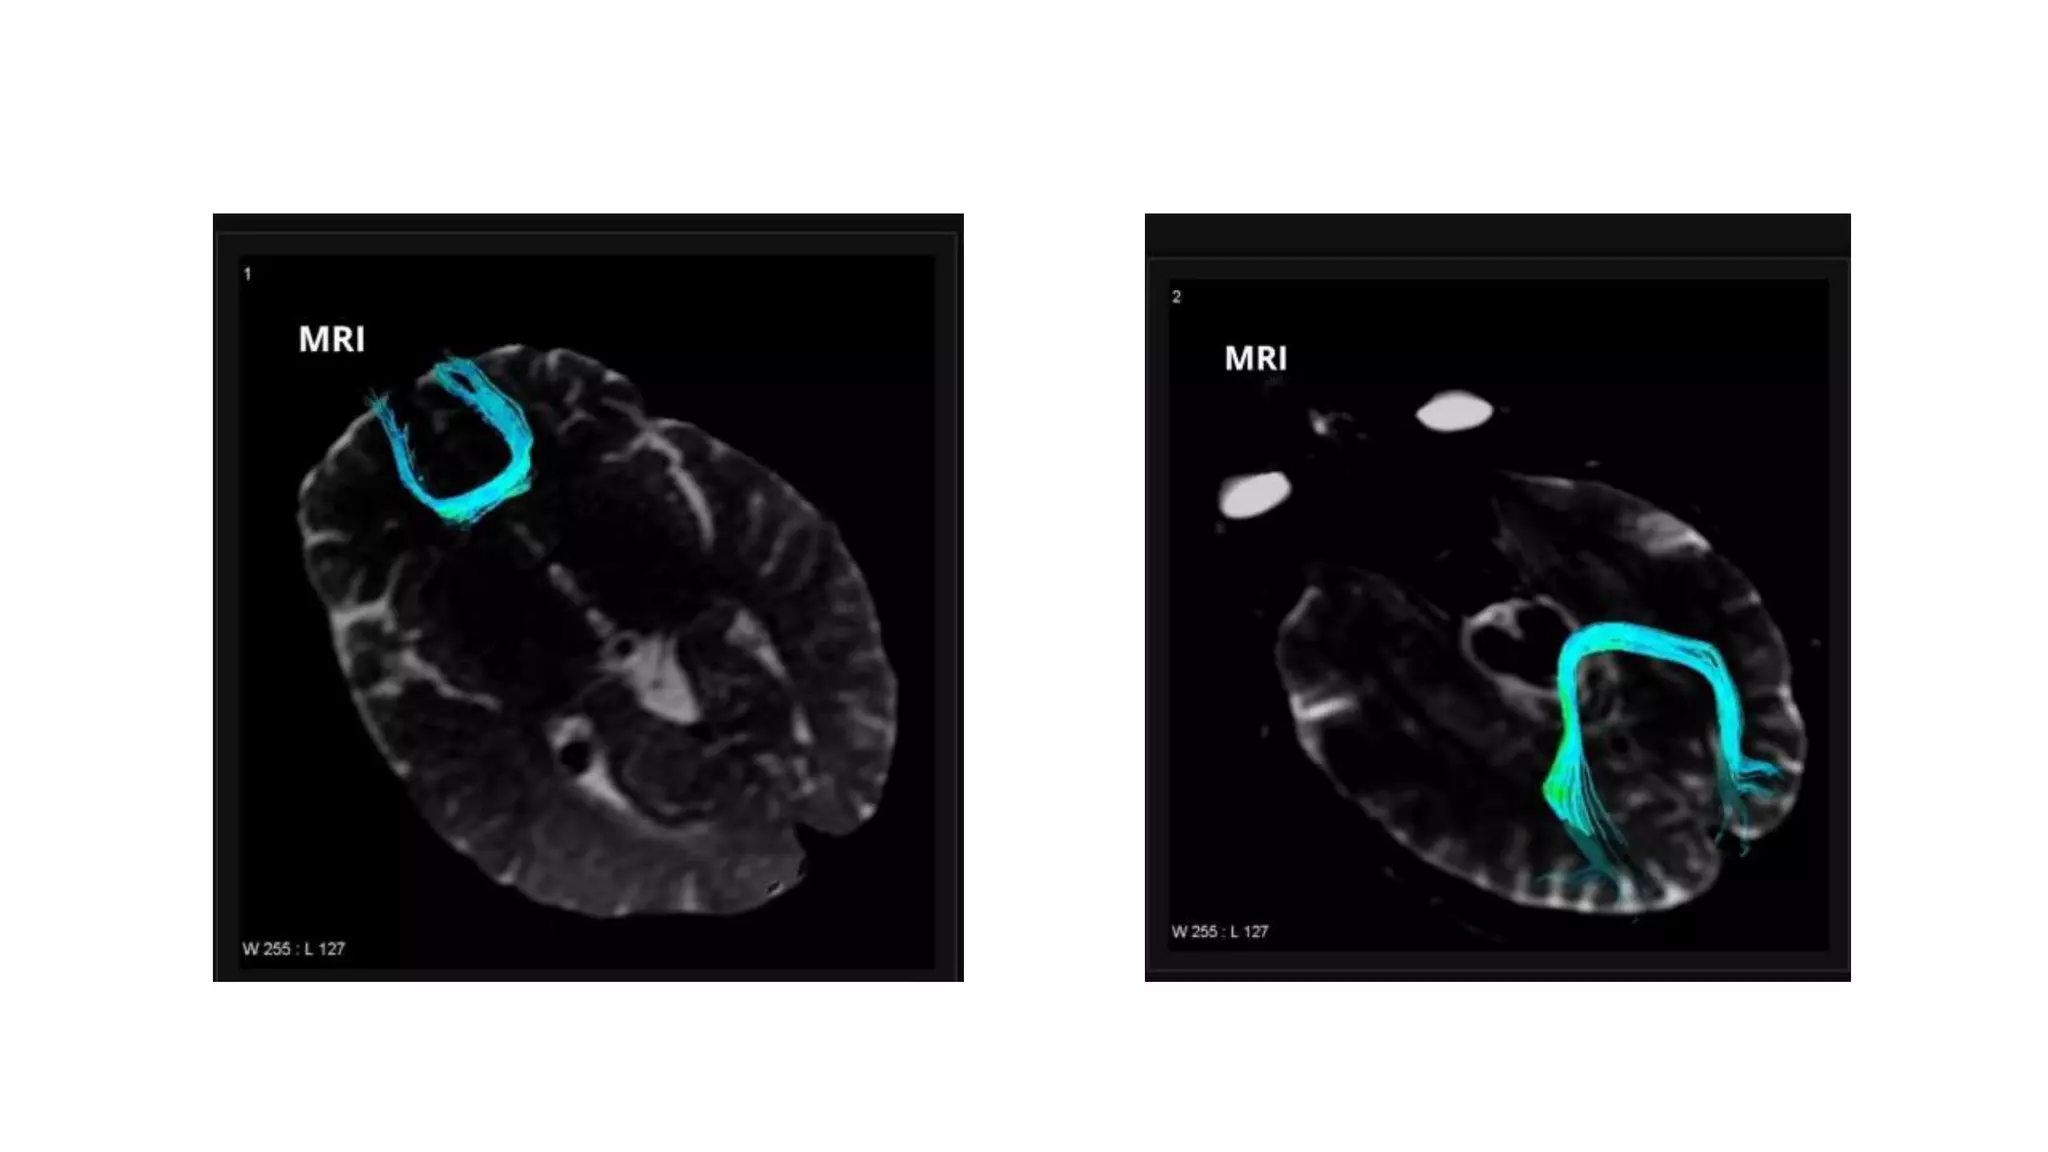

Association fiber: Cingulum

 An association fiber that allows the

communication between components of the

limbic system. Interconnect portion of frontal,

parietal and temporal lobe

 C –shaped structure located above the corpus

callosum and beneath the cingulate gyrus within

the medial surface of the brain

 Begins in the par-olfactory area of the cortex

below the rostrum of corpus callosum, then

courses within the cingulate gyrus, arching around

the corpus callosum, extends forward into the

para-hippocampal gyrus and uncus

Association fiber: Cingulum An association fiber that allows the communication between components of the limbic system. Interconnect portion of frontal, parietal and temporal lobe  C –shaped structure located above the corpus callosum and beneath the cingulate gyrus within the medial surface of the brain  Begins in the par-olfactory area of the cortex below the rostrum of corpus callosum, then courses within the cingulate gyrus, arching around the corpus callosum, extends forward into the para-hippocampal gyrus and uncus

• #26 Cingulum, sagittal view. A, Illustration shows the cingulum arching over the corpus callosum.B, Gross dissection, median view. C, Directional map. Because DTI reflects tract orientation voxel by voxel, the color changes from green to blue as the cingulum (arrows) arches around the genu and splenium (arrowheads). D-showing tractogram of cingulum Cingulum, axial directional map. The paired cingula (arrowheads) are easily identified in green at the section obtained just cephalad to the corpus callosum.